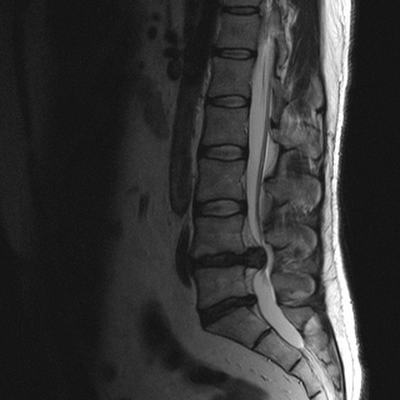

МРТ позвоночного столба: грыжа диска L4-L5 (сагиттальная плоскость, Т2 ВИ)

При патологических процессах снимки могут демонстрировать:

- протрузии, дегенеративные изменения (спондилодисцит, остеохондроз и др.), грыжи, признаки вовлечения в патологический процесс спинномозговых корешков;